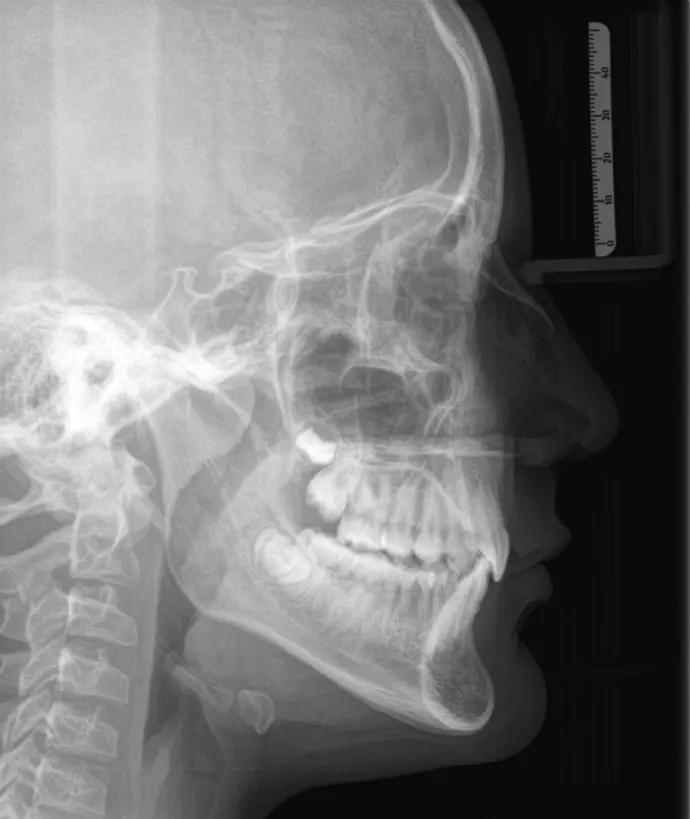

RX CEFALOMÉTRICA

Se obtiene una imagen de perfil de una región anatómica, manteniendo una alineación precisa y simétrica del paciente para evitar distorsiones. Este tipo de proyección permite observar con claridad las estructuras óseas y dentarias en el plano sagital, superponiendo de manera controlada ambos lados.